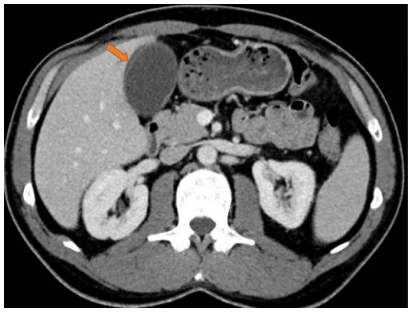

Observe o exame a seguir para responder as questões 39 e 40.

A seta em destaque aponta para

O método de imagem utilizado evidencia